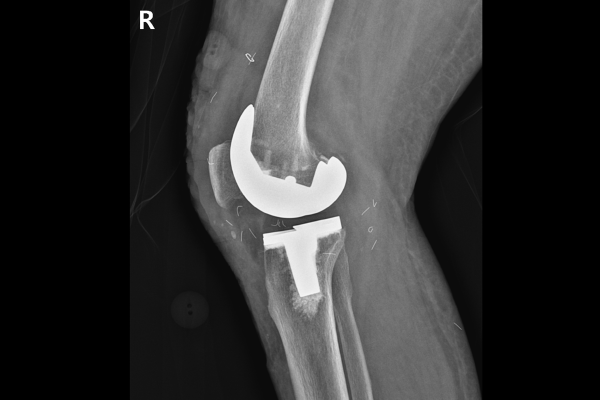

수술이 잘 마무리 되었고, 수술 후 X-RAY를 보면 환자분 무릎 관절에 딱 맞게 잘 치환된 것을 알 수 있습니다.

측면에서 확인했을 때 역시, 잘 치환되었음이 확인됩니다.